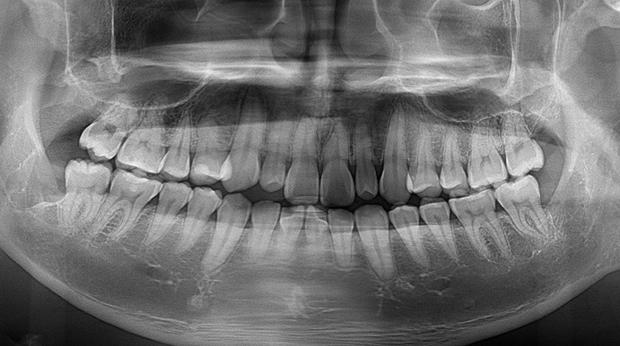

매복 사랑니 발치

임플란트와 사랑니 발치는 외과적 시술로 잇몸을 절개하는 외과적 시술은

짧으면 짧을 수록 시술 후 붓기와 통증이 최소화됩니다.

치과의사 경력 14년차 구강외과 전문의가 빠르고 안전하게, 아프지 않게 수술해 드립니다.

치과경력 14년차 구강외과 전문의

연세대학교 치과대학 구강외과 임상 조교수